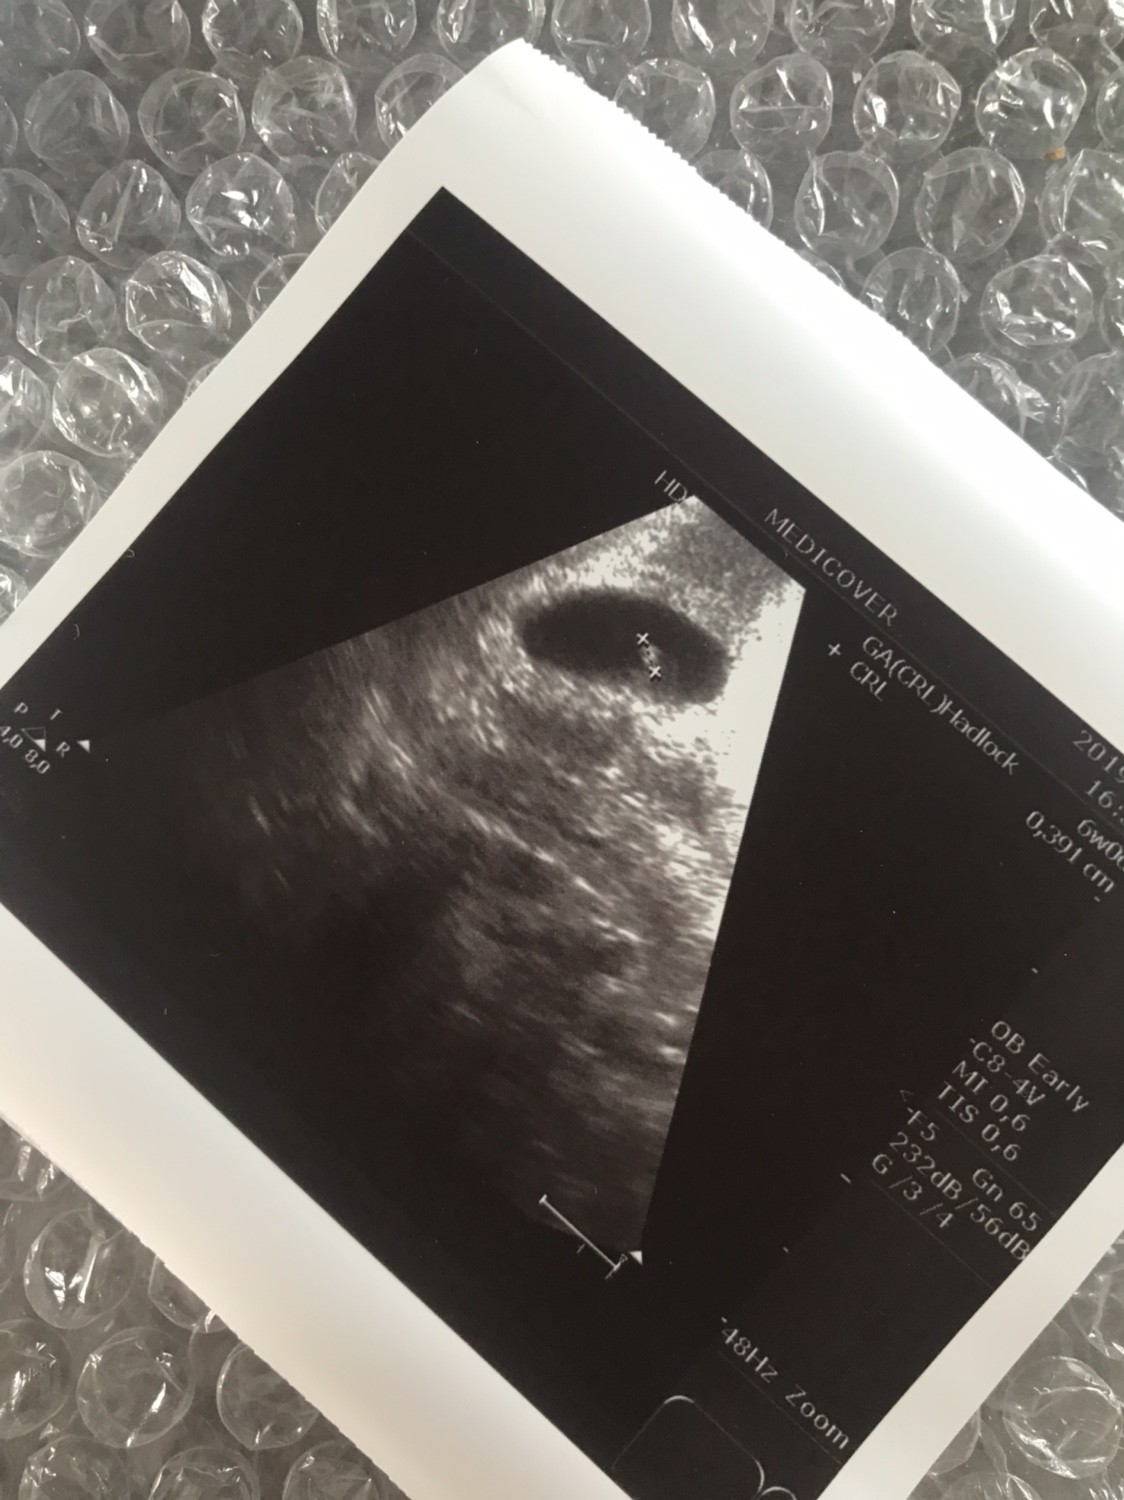

11.07 miałam @test ciążowy wychodził mi pozytywny już w 24dc. Zrobiłam bete: 26dc 95, 28dc 294, 31dc 1148 (godz 18.00), 33dc 2250 (godz 8:30). Wczoraj byłam u lekarza, według om byl to 5tc+5 a z usg 5tc+2. Widoczny był tylko pęcherzyka i zmartwilam się że nic więcej nie zobaczył mimo że owulacje miałam w 13/14dc. Mam przyjść za tydzień, ale trochę się podlamalam. Czy ktoś miał podobna sytuacje? Czy mimo wzrastającej wcześniej bety ich może się teraz ciąża nie rozwijać prawidłowo czy to za wcześnie na zarodek?

Ja byłam 5+2 i widać było zarodek ale dosłownie jak taka główkę od szpilki

Nawet na zdjęciu ciężko ja zobaczyć

D9F18178-B8CC-496E-BA5C-270DF75BDF66.jpg

A tu tydzień później

IMG_8306.JPG